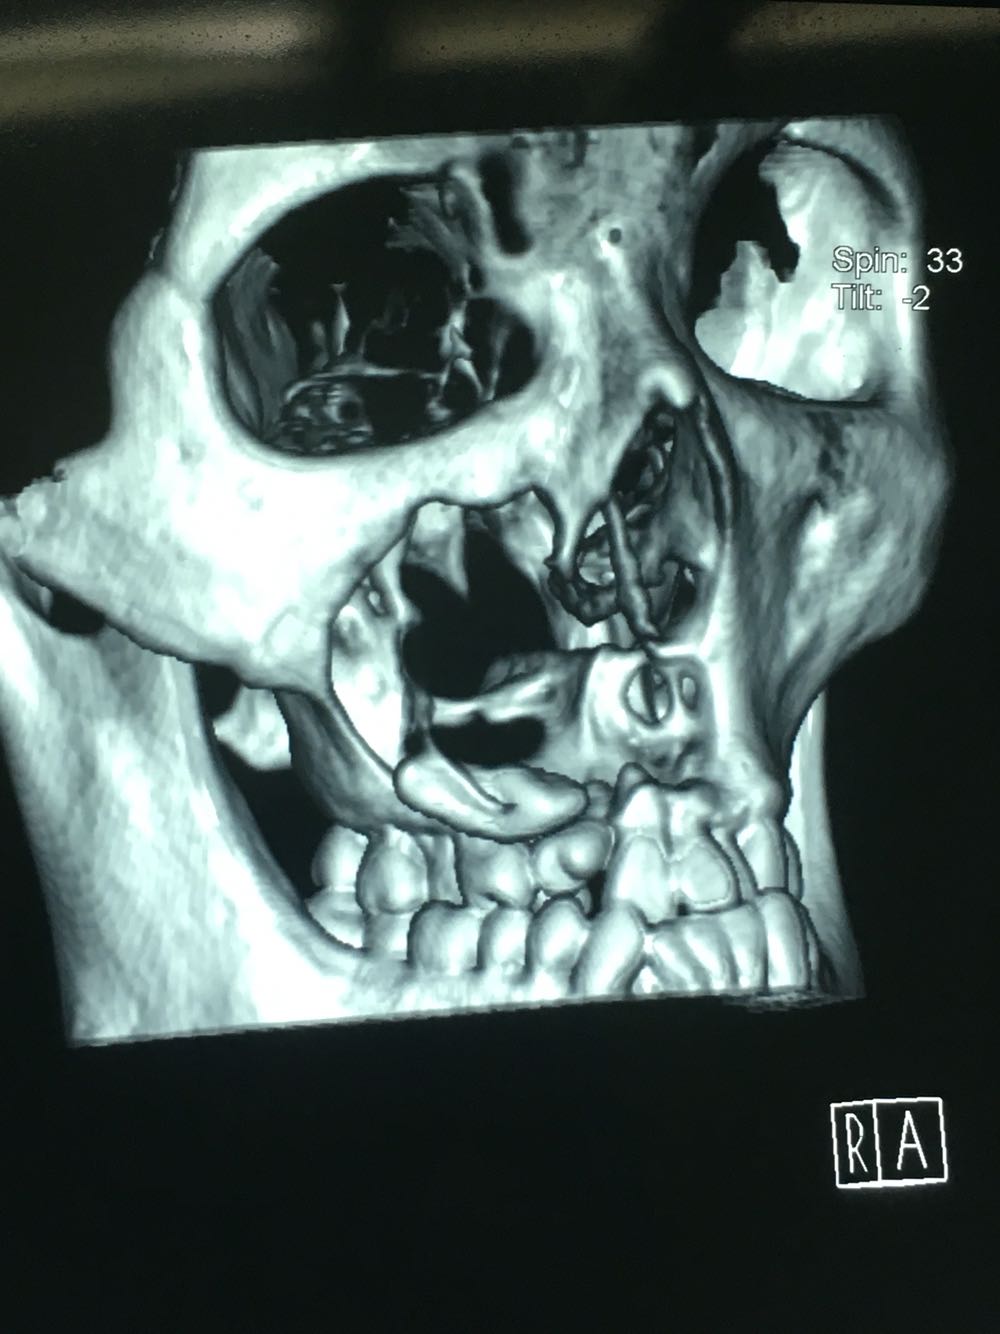

查体:面部明显不对称,右上颌膨隆明显,右鼻翼抬高,眶下区无麻木感,眼球运动自如,13牙齿缺如,16-22牙齿唇侧前庭肿胀,中央扪及波动感,边缘乒乓感,相关牙齿1度松动。 辅查:穿刺,抽得淡黄色液体,全景及CT,上颌骨囊肿,右侧上颌骨骨质大部分破坏

诊断:右上颌骨囊肿,13埋伏阻生。 治疗:开窗减压,拔除13阻生牙齿